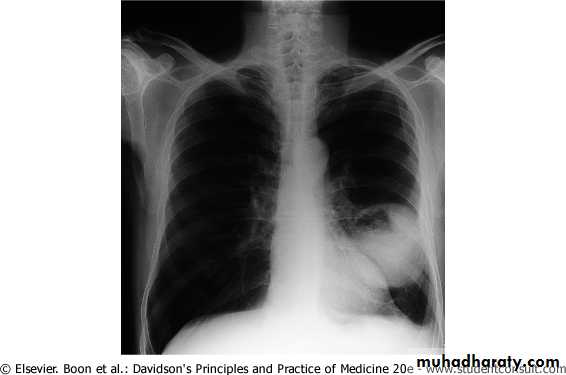

The main aims of investigations are to confirm the diagnosis, establish the histological cell type and define the extent of the disease.1- CXR: common radiological features of lung cancer:

Unilateral hilar enlargement.

Peripheral pulmonary opacity.

Lung, lobe or segmental collapse.

Pleural effusion.

Broadening of mediastinum, enlarged cardiac shadow, elevation of a hemidiaphragm.

Rib destruction.